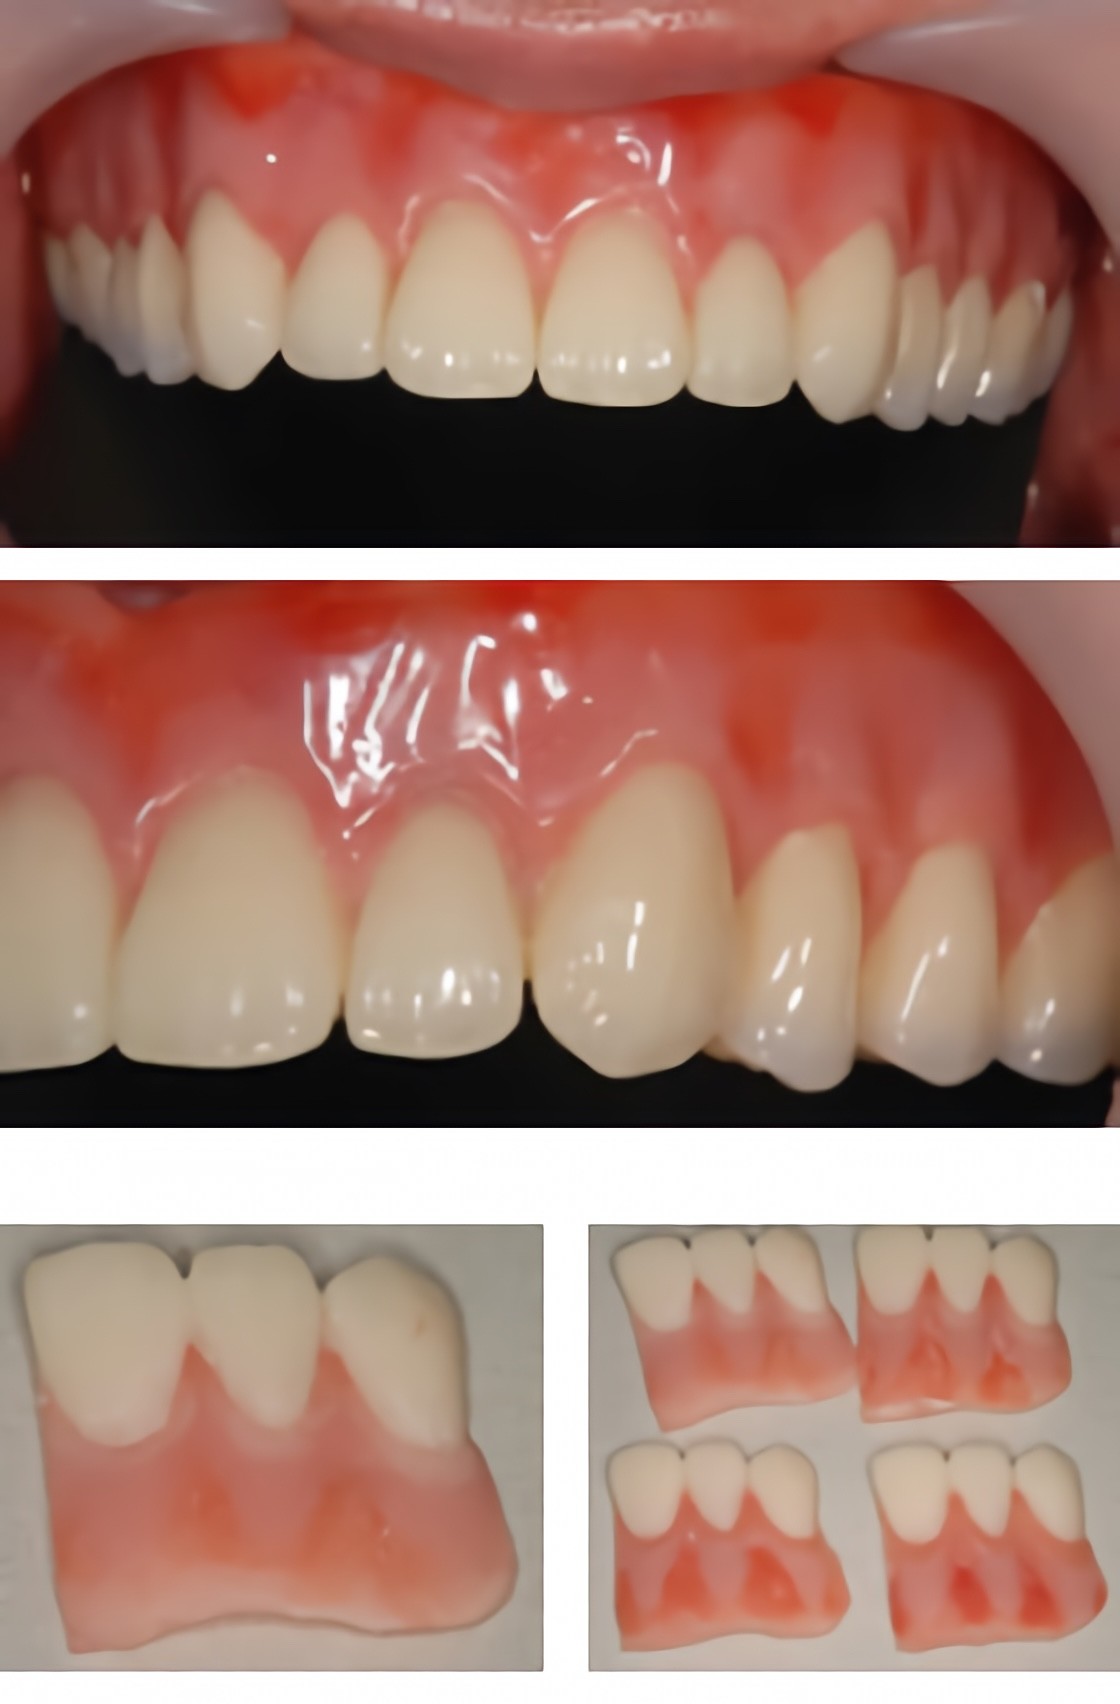

カラーリングデンチャー

クボタ歯科醫院では、失われた歯の機能を補い、日常生活を快適に過ごせるよう義歯(入れ歯)治療に取り組んでいます。噛む機能の回復だけでなく、見た目の自然さや装着時の違和感を抑えることも大切にしています。

義歯は素材や設計によって使用感が大きく異なります。メタルフレームデンチャーは、薄くて軽い金属を使用することで、装着時の違和感を抑えつつ高い耐久性が期待できます。食事中の温度が伝わりやすい点も特徴です。

見た目を重視したい患者様には、金属のバネが目立ちにくいノンクラスプデンチャーを提案しています。自然な口元を保ちやすく、会話や笑顔の際にも義歯が気になりにくい設計です。歯ぐきへの負担を軽減したい場合には、やわらかい素材を用いたシリコンデンチャーにも対応し、装着時の痛みや違和感を和らげています。

義歯は作製後の調整やメインテナンスが重要です。クボタ歯科醫院では、使用感や噛み合わせを確認しながら、長く快適に使い続けられるようサポートしています。